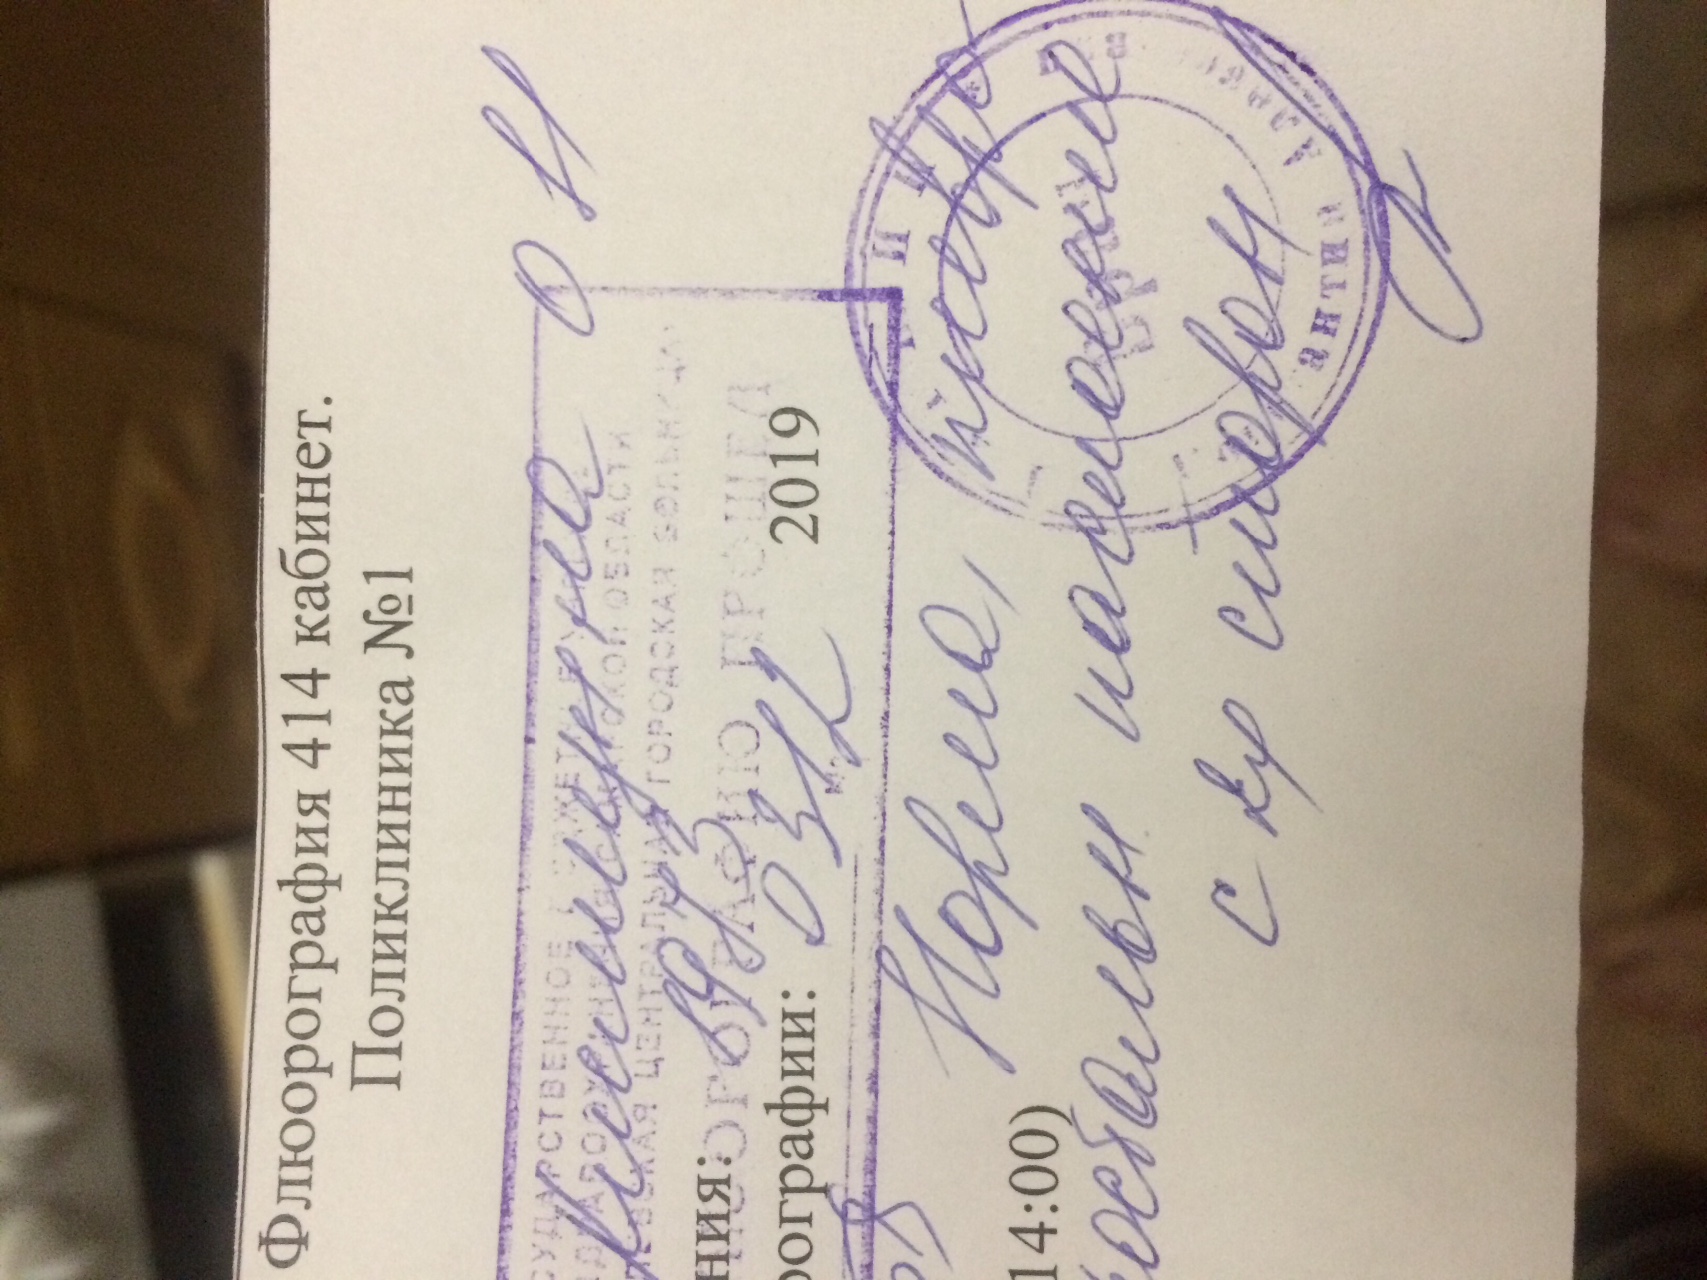

Фотографии рентгеновских снимков без необходимости направления от врача